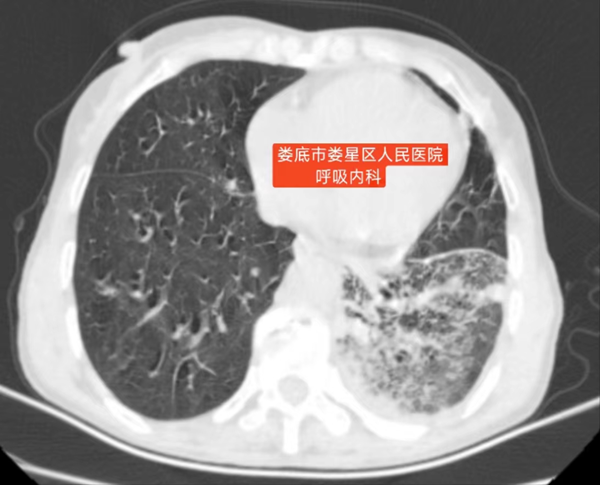

经验性抗感染治疗通常有效,这次却没起作用。肺部CT能看到感染病灶,但病魔很顽固,高热反复,每次体温上升都很危险。感染原因不明,常规手段找不到根源,面对未知病原体的威胁,急需找到新的突破口。

医疗团队果断改变策略,进行支气管镜检查。通过这项微创操作获取标本,培养结果显示,感染王阿姨呼吸道的是不常见的诺卡菌。正因为诺卡菌对普支气管镜锁定罕见诺卡菌挽救七旬老人通抗生素不敏感,之前的治疗才没效果。这个精准诊断为调整治疗方案指明了方向。